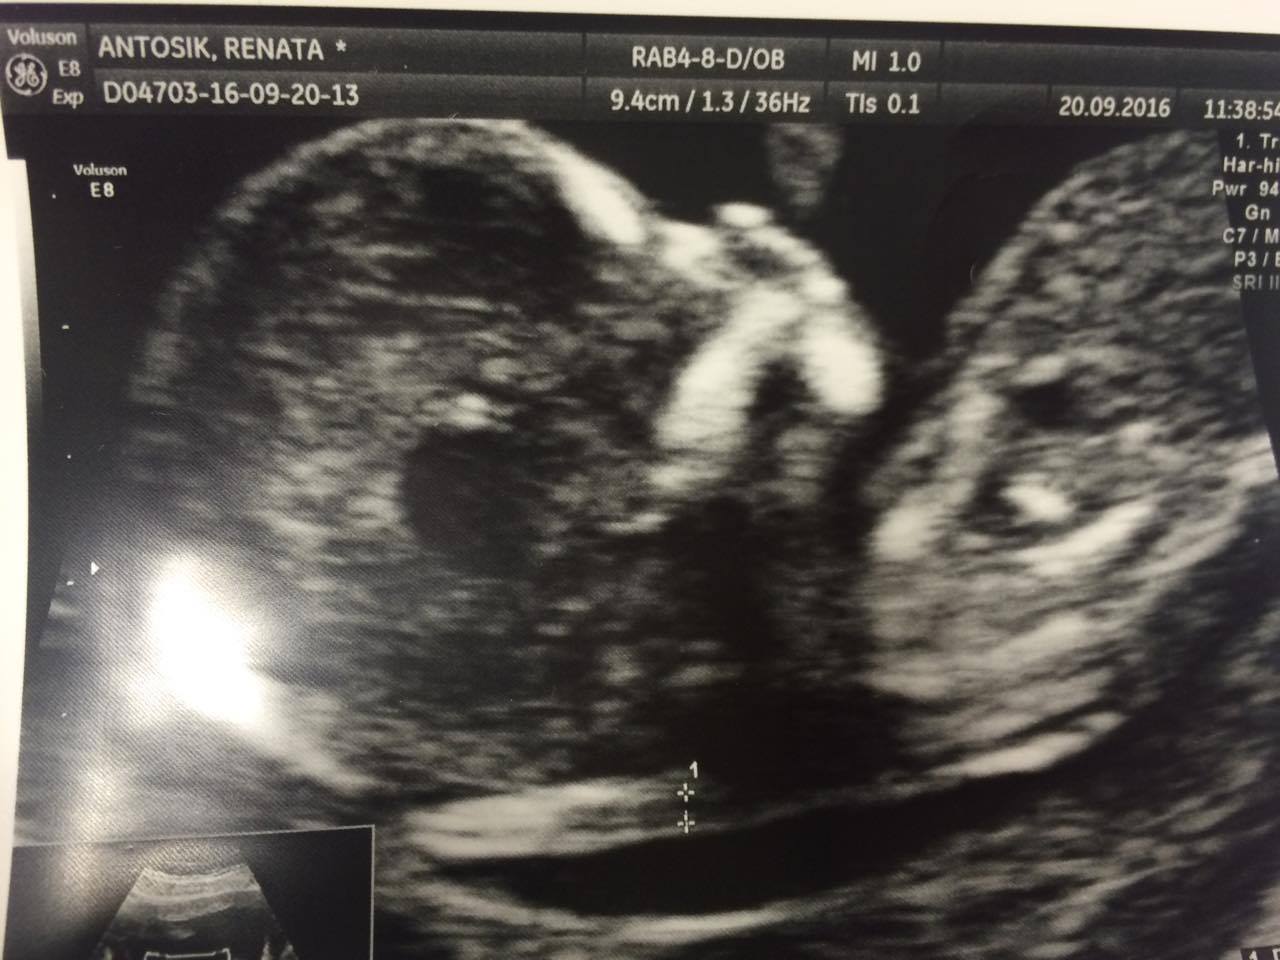

Ja chodziłam do dr Chojnackiego przyjmuje na piątkowe. Ale niestety w Anglii nie mam wyboru ale mam lekarza którego z miłą chęcią zabrała bym do Polski na poród. Też mam co wizyte sprawdzana szyjke czy śluz dobry itp. Jak to mój lekarz mówi jestem zamknięta na 4 spusty [emoji4] do tego usg 2d i 3d i bicie serduszka [emoji4] jest naprawdę godny polecenia! Tylko szkoda że daleko [emoji57]Ja moge polecic ale z Poznania![]()